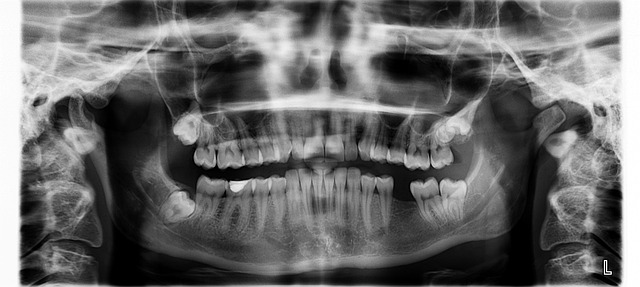

치주 상태, 잇몸 두께, 뼈 높이·폭, 교합을 종합 평가합니다. 이 단계의 정밀도가 전체 시술 성공률과 기간에 직접적인 영향을 줍니다. 통상 1~2회 내원으로 계획이 확정되며, 빠르면 1일, 평균 3~5일 안에 임플란트 시술기간 초안이 나옵니다.

3) 골융합(Osseointegration)

임플란트와 뼈가 안정적으로 결합되는 생물학적 기간입니다. 하악은 평균 2개월, 상악은 3~4개월이 일반적입니다. 흡연, 혈당 조절 불량, 구강 위생 불량은 이 기간을 늘리고 실패 위험을 높여 전체 임플란트 시술기간을 지연시킬 수 있습니다.